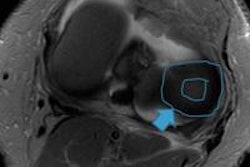

The 10-year prospective study of single longitudinal meniscus repairs in the central third avascular region used 3-tesla MRI cartilage-sensitive pulse sequences, including T2 mapping, to define meniscus function. Preservation of the meniscus is paramount for long-term knee joint function.

A subset of 16 patients who underwent 17 meniscus repairs before the age of 20 received long-term follow-up. All but one patent had concomitant ACL reconstruction. The researchers conducted 3-tesla MRI evaluations on 12 lateral and five medial menisci between 12 and 22 years postoperatively.

The 3-tesla MR images showed retention of the coronal and sagittal position of the menisci without extrusion in 13 knees and with slight extrusion in four knees. A displaced meniscus tear that extended onto both surfaces also was noted in four knees.